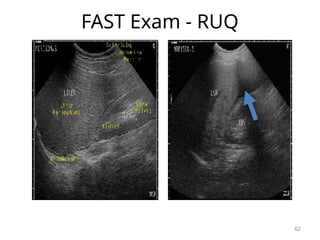

FAST Exam

• Focused Abdominal Sonography in

Trauma

• Has largely replaced deep peritoneal

lavage (DPL)

• Bedside ultrasound looking for blood

collection in an unstable patient.

• If the patient is unstable and a blood

collection is found, proceed emergently

to the operating theater.

59

FAST

• Sensitivity of 94.6%

• Specificity of 95.1%

• Overall accuracy of 94.9% in identifying

the presence of intra-abdominal

injuries.

– Yoshil: J Trauma 1998; 45

60

Right Upper Quadrant - Morrison’s

Pouch

• Between the liver and kidney in RUQ.

• First place that fluid collects in supine

patient.

61

FAST Exam - RUQ

62